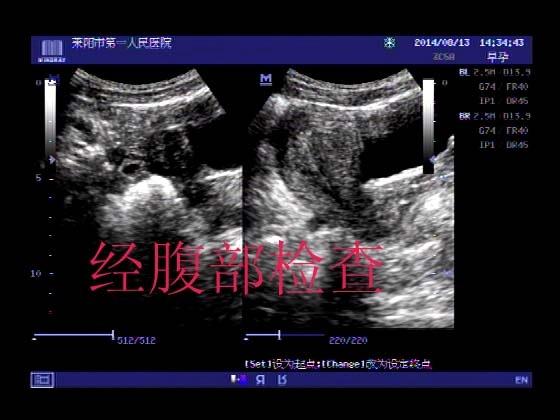

超声入门贴341:宫外孕(阴超的魅力)

女,32岁,停经15天,

一周前在上极医院检查:化验尿HCG阳性,血HCG400多,超声检查问见明显孕囊,让随访。

很典型,图像不错,阴超的优势!!